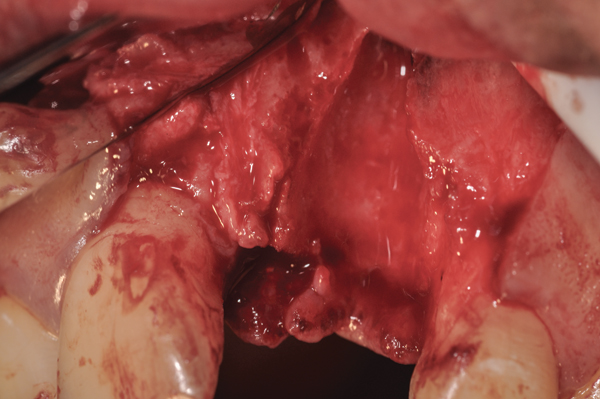

Fig 10. At 3 months postoperative, the flap was elevated, demonstrating a restored buccal plate of bone.

Figure 10

Fig 11. An implant was placed in regenerated bone.

Figure 11